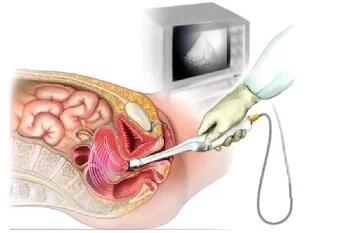

سونوگرافی آنومالی جنین چیست و چرا انجام میشه؟

سونوگرافی آنومالی یک نوع اسکن برای تشخیص ناهنجاری های احتمالی جنین است و در سه ماهه دوم بارداری انجام می شود و معمولا اسکنی دقیق است.